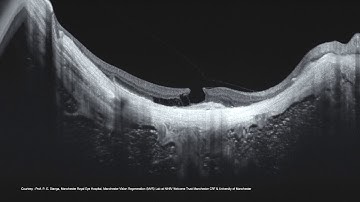

Full Cornea En-Face OCT Navigation using TOPCON Triton